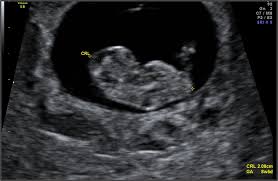

Dating scan £48 .00 . Suitable between 7-13 weeks Available for women above the age of 16 . 2D scan to confirm an intrauterine pregnancy; Visualisation of Heartbeat; Confirmation of estimated dating of your pregnancy; Check for single or multiple pregnancy; Report provided; Complete with one black and white print

Baby Scanning Boutique is a brand new non-diagnostic baby scanning boutique, in North Wales between Wrexham and Chester . We offer early scans from 6 weeks and gender scans , 2D, 3D, 4D and HD Live scans from 14 weeks to help you prepare for the new addition to your family . Here at Baby Scanning Boutique we offer a variety of packages to provide . . .

One of the only regulated ultrasound clinics in the UK to offer HD baby scans . A convenient central location easily accessible from across Cheshire and North Wales . A comprehensive range of 2D, 3D and 4D pregnancy scans , with prices starting at just £45 . The very latest in advanced HD ultrasound technology .